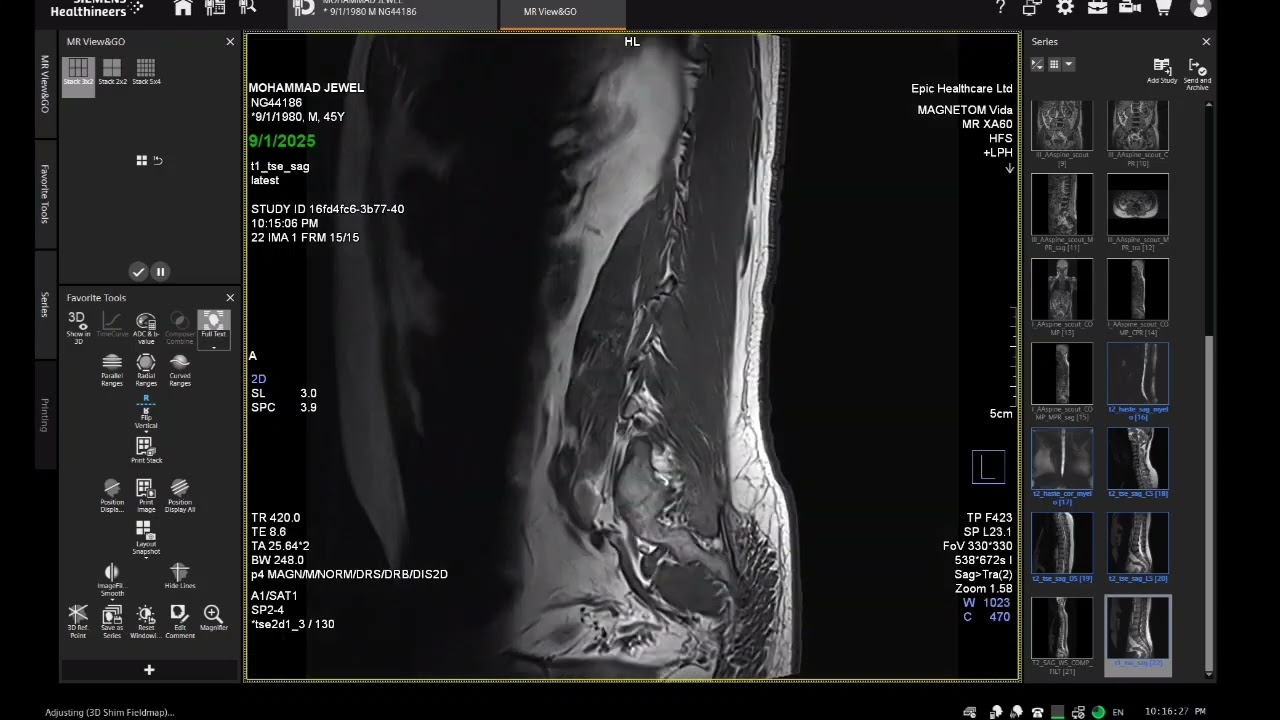

MRI of Lumber Spine Techniques & Filming Process || How to MRI lumber spine in magnetom vida 3T|| скачать в хорошем качестве

MRI of Lumber Spine Techniques & Filming Process || How to MRI lumber spine in magnetom vida 3T||